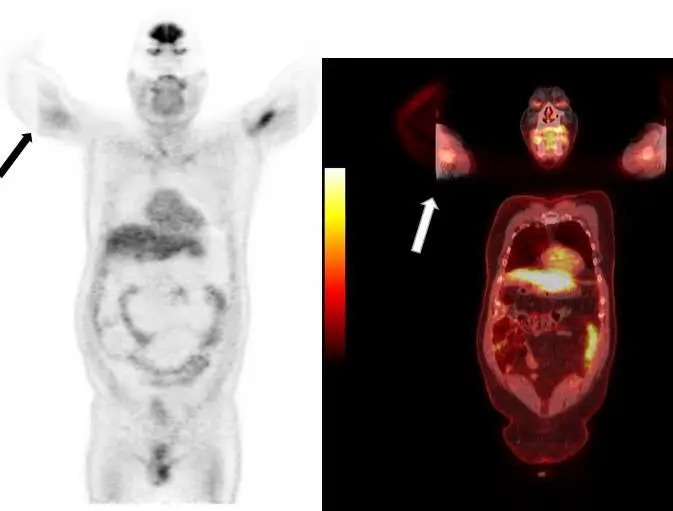

下圖是 PET 影像,箭頭所指的斷面假影為下列何者造成?

- 左圖(PET MIP 影像):這是一張全身 PET 的最大強度投影(maximum intensity projection, MIP)影像。病患採雙手舉高(arms-up)的姿勢。黑色箭頭所指處為病患的右手臂,可以明顯觀察到右手臂的外側出現一條非常平直、銳利的垂直切面,手臂的遠端部分完全消失(被截斷)。

- 右圖(PET/CT 融合影像):這是一張冠狀面(coronal view)的 PET/CT 融合影像。白色箭頭同樣指向病患的右手臂。在此處不僅 CT 軟組織影像出現不自然的垂直邊界,PET 的活度分佈也在此邊界戛然而止,這反映了超出 CT FOV 的區域因為缺乏衰減校正數據,導致該區域的 PET 影像無法正確重建與顯示。